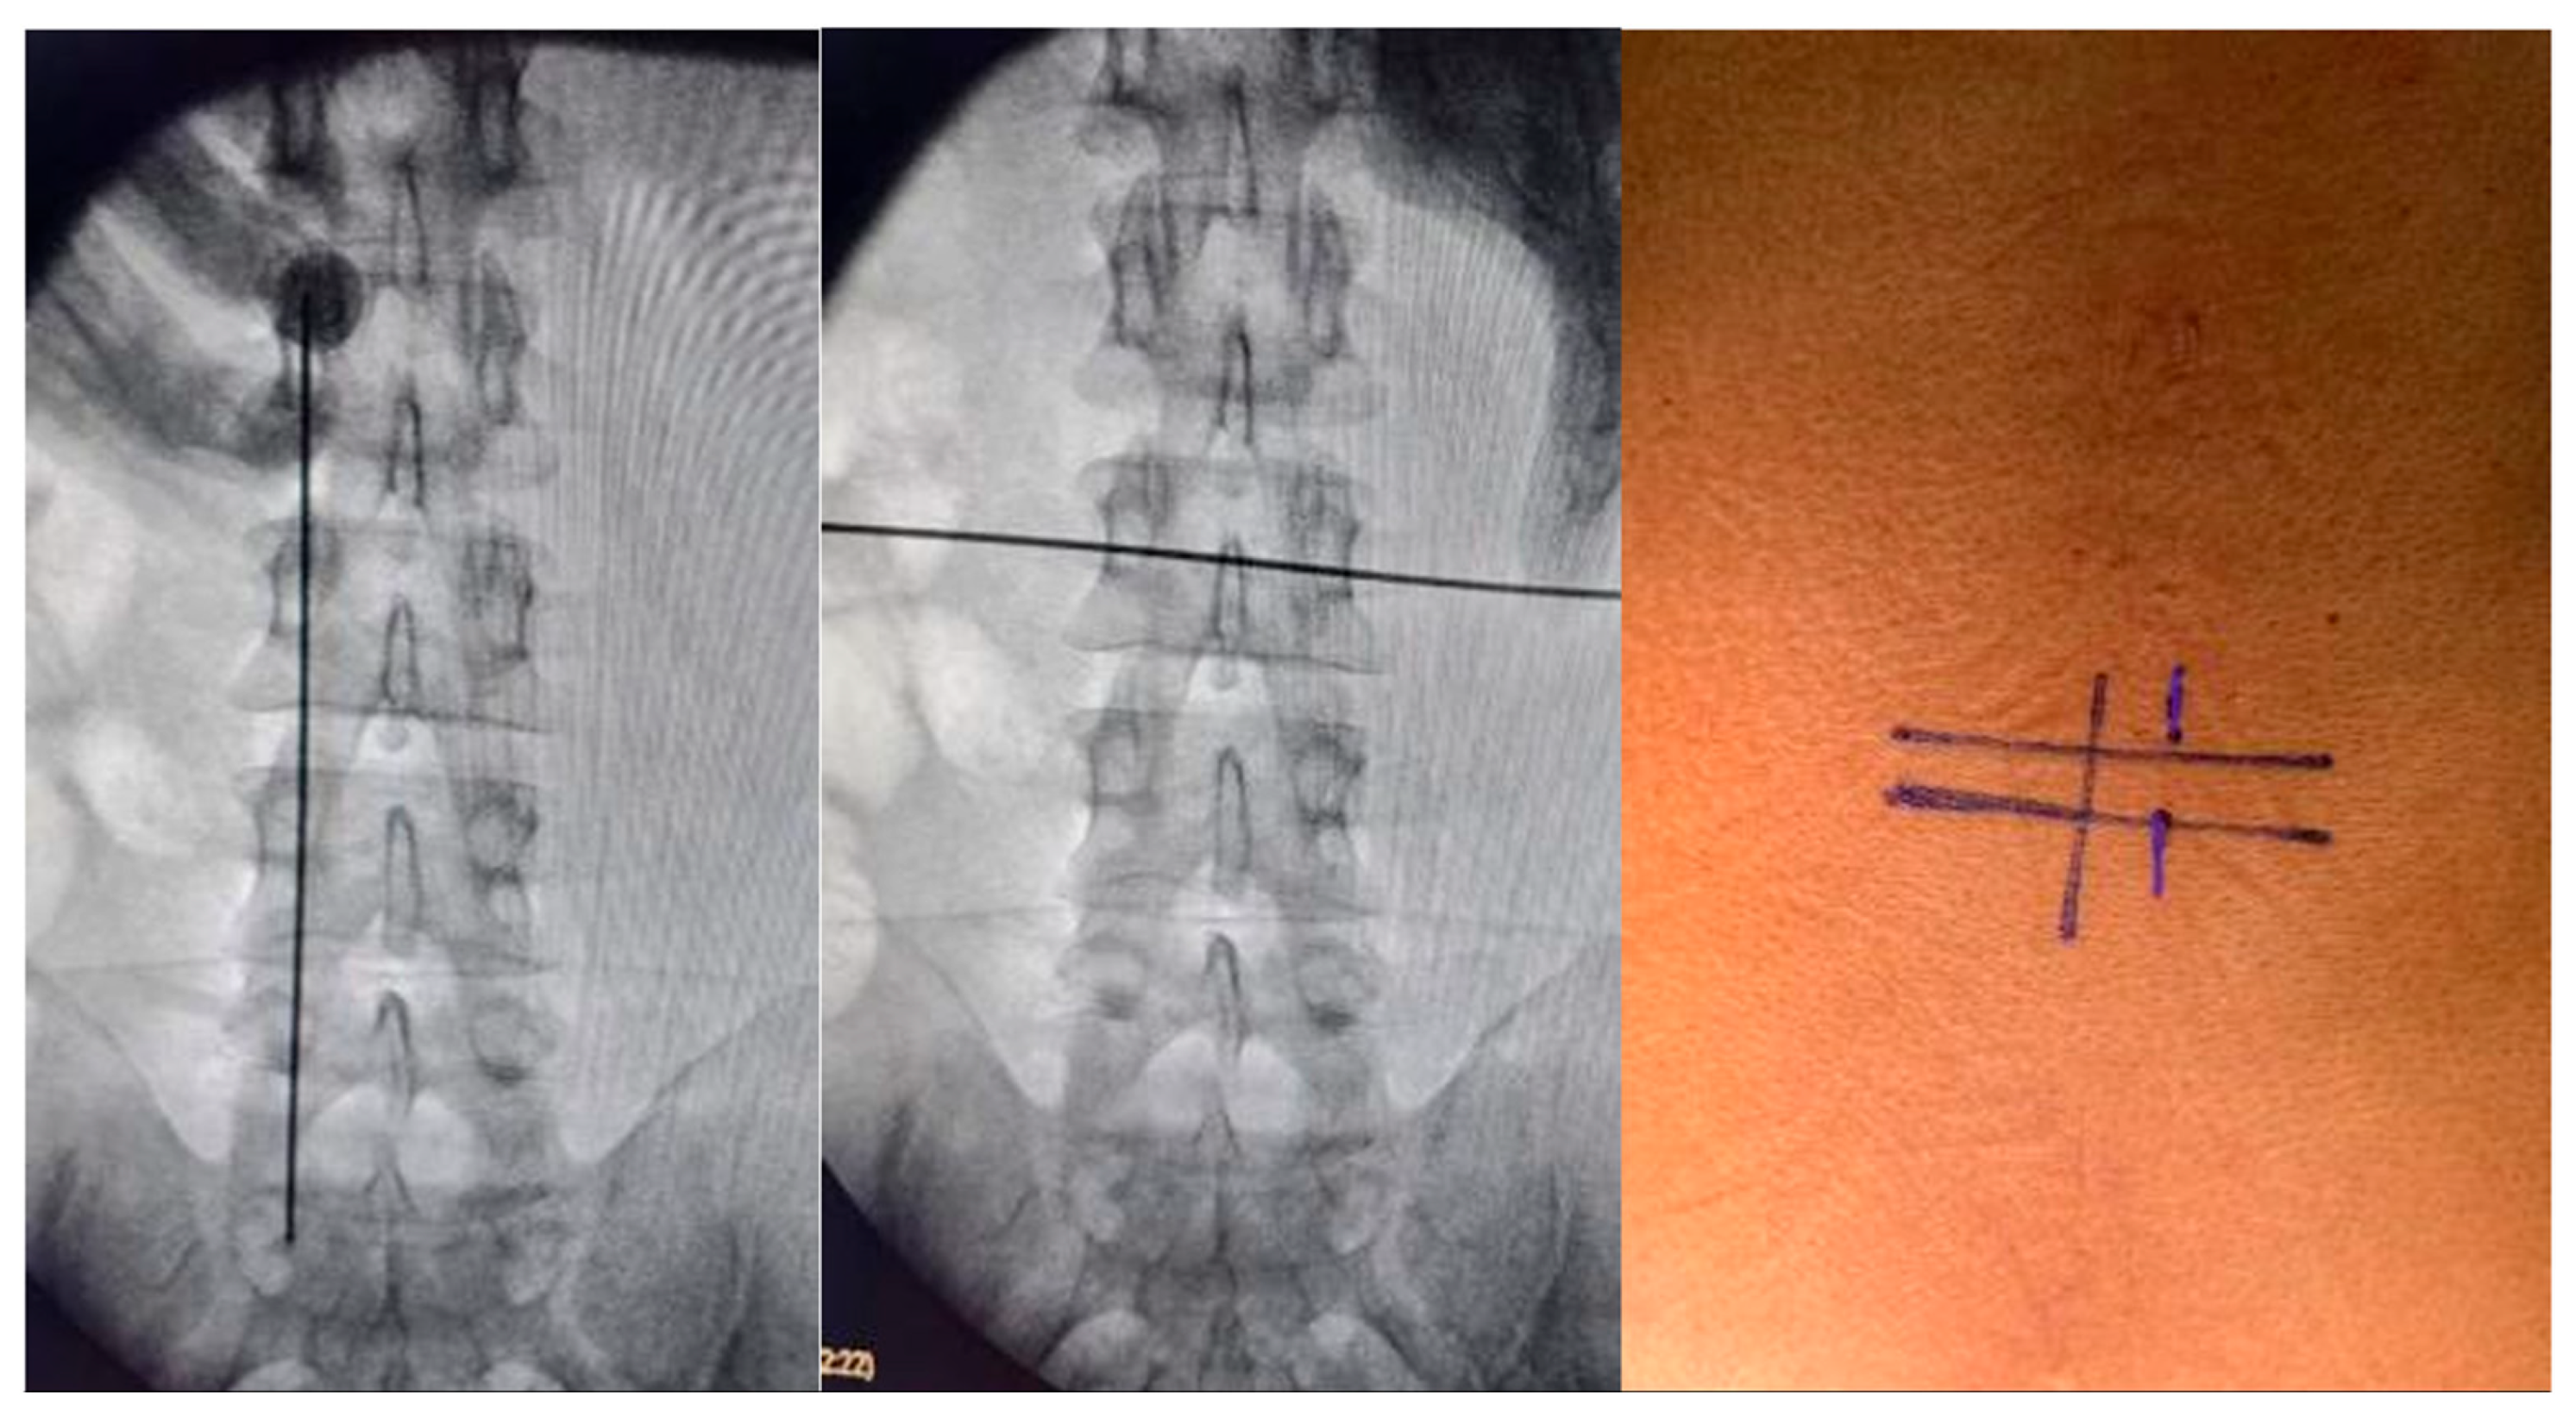

2.1. Surgical Technique

Surgical planning involved the UBE technique via two small incisions. A right-sided approach was utilized in 8 cases and a left-sided approach in 3 cases. Localization was achieved using fluoroscopic landmarks: the mid-pedicular lines for the right-sided approach and infra-pedicular lines in the horizontal plane for the left-sided approach, along with the medial pedicular line in the vertical plane. We recommend obtaining Anteroposterior and lateral images to confirm location; this ensures optimal tissue mobility and flexibility at the time of durotomy and tumor dissection. While a midline durotomy is generally recommended, this can be modified depending on the location of the lesion. The patient was positioned prone on a radiolucent operating table. The operating room was set up in the standard fashion for biportal endoscopic surgery (

Figure 1,

Figure 2 and

Figure 3).

Surgical intervention was performed using the UBE technique via a right-sided approach based on spinometric landmarks (

Figure 2), with minimal muscular tissue disruption. Bilateral laminotomy of the cephalic and caudal laminae was completed with a wider “O-cut” using the over-the-top technique, followed by flavectomy using Kerrison rongeurs and curettes. A midline durotomy was performed with a #11 scalpel blade, and the incision was extended with a Rhoton dissector. Following visualization of the tumor, dissection was performed with Rhoton and Penfield dissectors. Hydrostatic dissection was facilitated by temporarily increasing the pump flow, after which the lesion was extracted with pituitary forceps without complications. Dural closure was achieved with a 6-0 prolene suture using the previously described technique (

Figure 3).